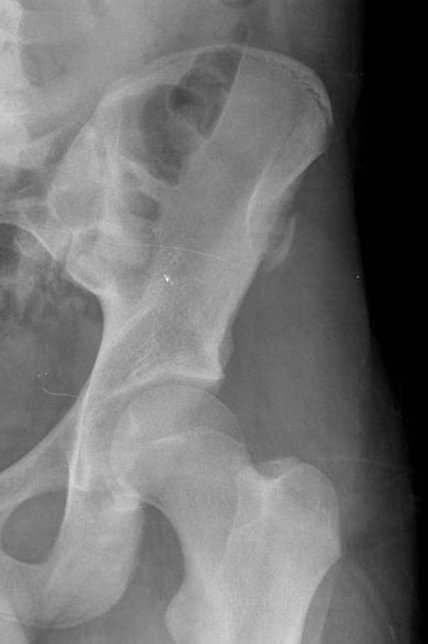

Once healing starts these lesions may mimic the appearance of an osteosarcoma, unfortunately so may the histology.

Anterior-Superior Iliac Spine Avulsion

This is the attachment of the sartorius and tensor fascia lata muscles.